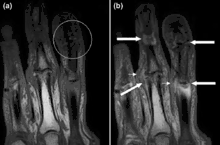

Magnetic resonance images of the fingers in psoriatic arthritis. Shown are T1 weighted axial (a) pre-contrast and (b) post-contrast images exhibiting dactylitis due to flexor tenosynovitis at the second finger with enhancement and thickening of the tendon sheath (large arrow). Synovitis is seen in the fourth proximal interphalangeal joint (small arrow).